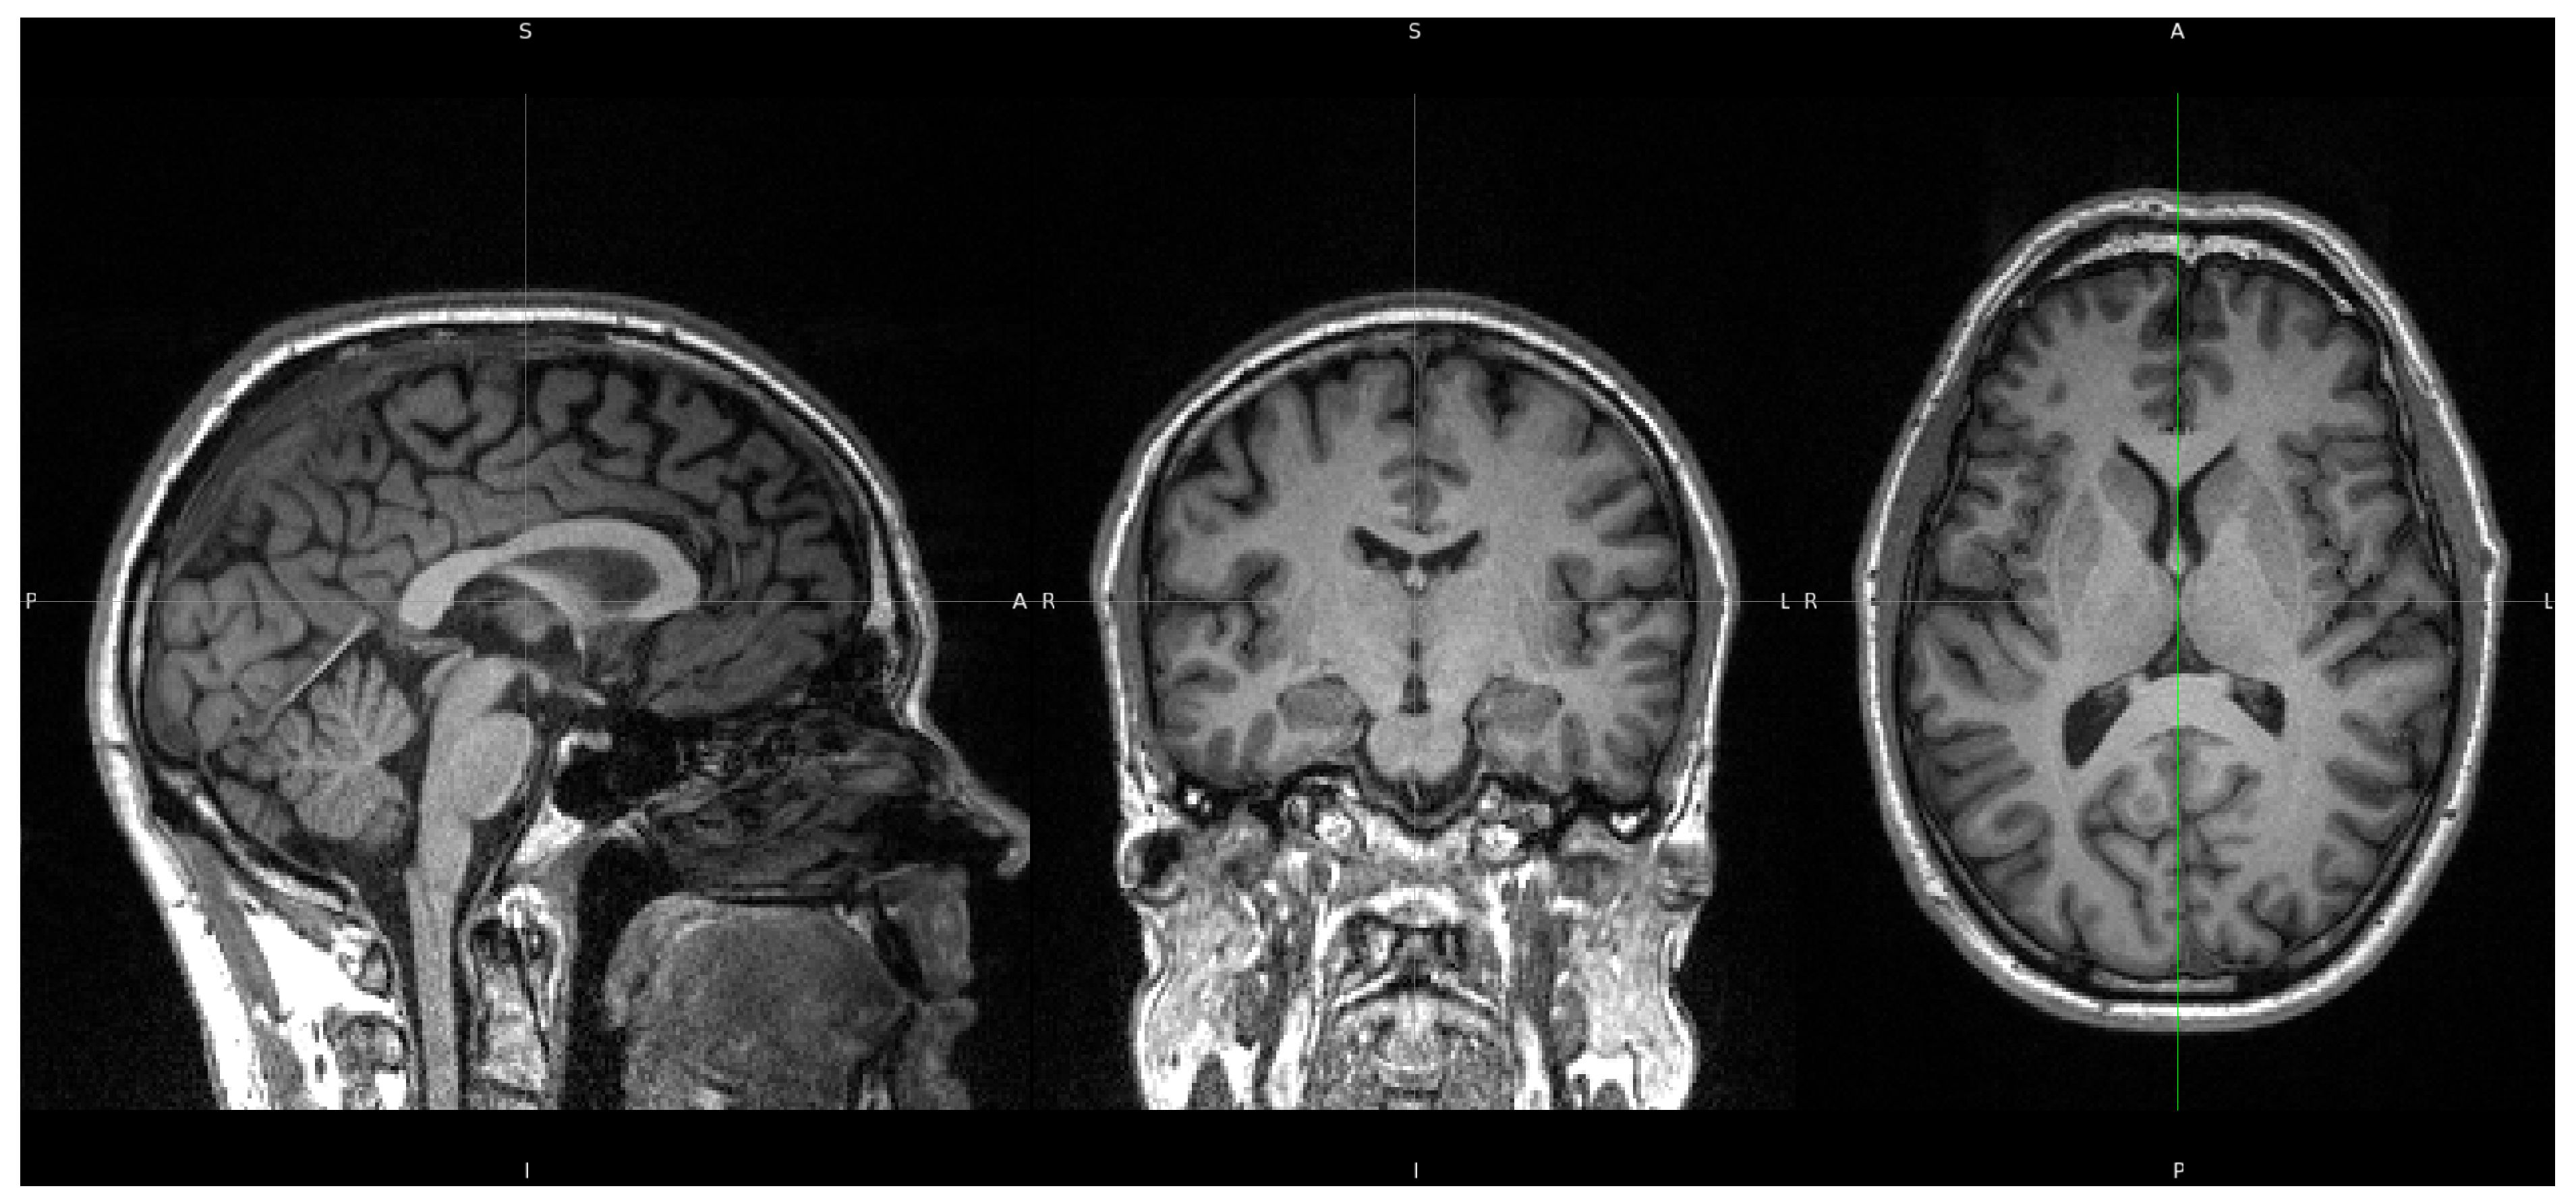

For the current morphometric analyses, we utilized only the high-resolution T1-weighted images, acquired using a 3D MPRAGE (Magnetization Prepared Rapid Gradient Echo) sequence. The acquisition parameters included a spatial resolution of 1.0 mm isotropic ( 1 × 1 × 1 mm3) across 192 sagittal slices, with repetition time (TR) of 2500 ms, echo time (TE) of 2.26 ms, and inversion time (TI) of 900 ms. The field of view (FOV) was set to 256 × 256 mm2 with a corresponding matrix size of 256 × 256, and parallel imaging was employed using GRAPPA with an acceleration factor of 2.

Figure 1 shows a representative T1-weighted image from our dataset, demonstrating the high tissue contrast necessary for accurate morphometric analysis. The corresponding FreeSurfer-generated segmentation mask, which forms the basis for our morphometric measurements, is illustrated in Figure 2. These images exemplify the quality standards maintained throughout our dataset.